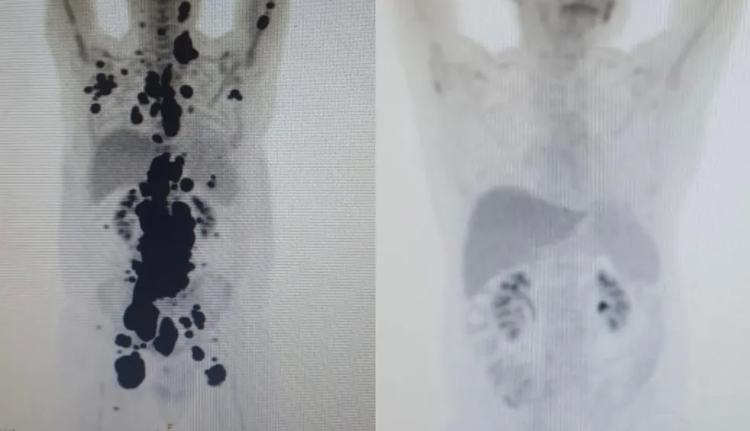

Paciente teve remissão completa - Com verbas da Fundação de Amparo à Pesquisa do Estado de São Paulo (Fapesp) e do Conselho Nacional de Desenvolvimento Científico e Tecnológico (CNPq), 14 pacientes foram tratados com o CAR-T Cell e todos tiveram remissão de ao menos 60% dos tumores.

Paulo Peregrino, de 61 anos, estava há 13 anos lutando contra o câncer e teve remissão completa após um mês de tratamento. Ele estava prestes a receber cuidados paliativos quando foi selecionado para o teste.